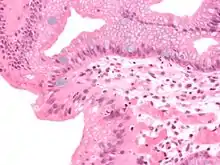

Micrograph of a gastro-esophageal junction with pancreatic acinar metaplasia. The esophageal mucosa (stratified squamous epithelium) is seen on the right. The gastric mucosa (simple columnar epithelium) is seen on the left. The metaplastic epithelium is at the junction (center of image) and has an intensely eosinophilic (bright pink) cytoplasm. H&E stain.